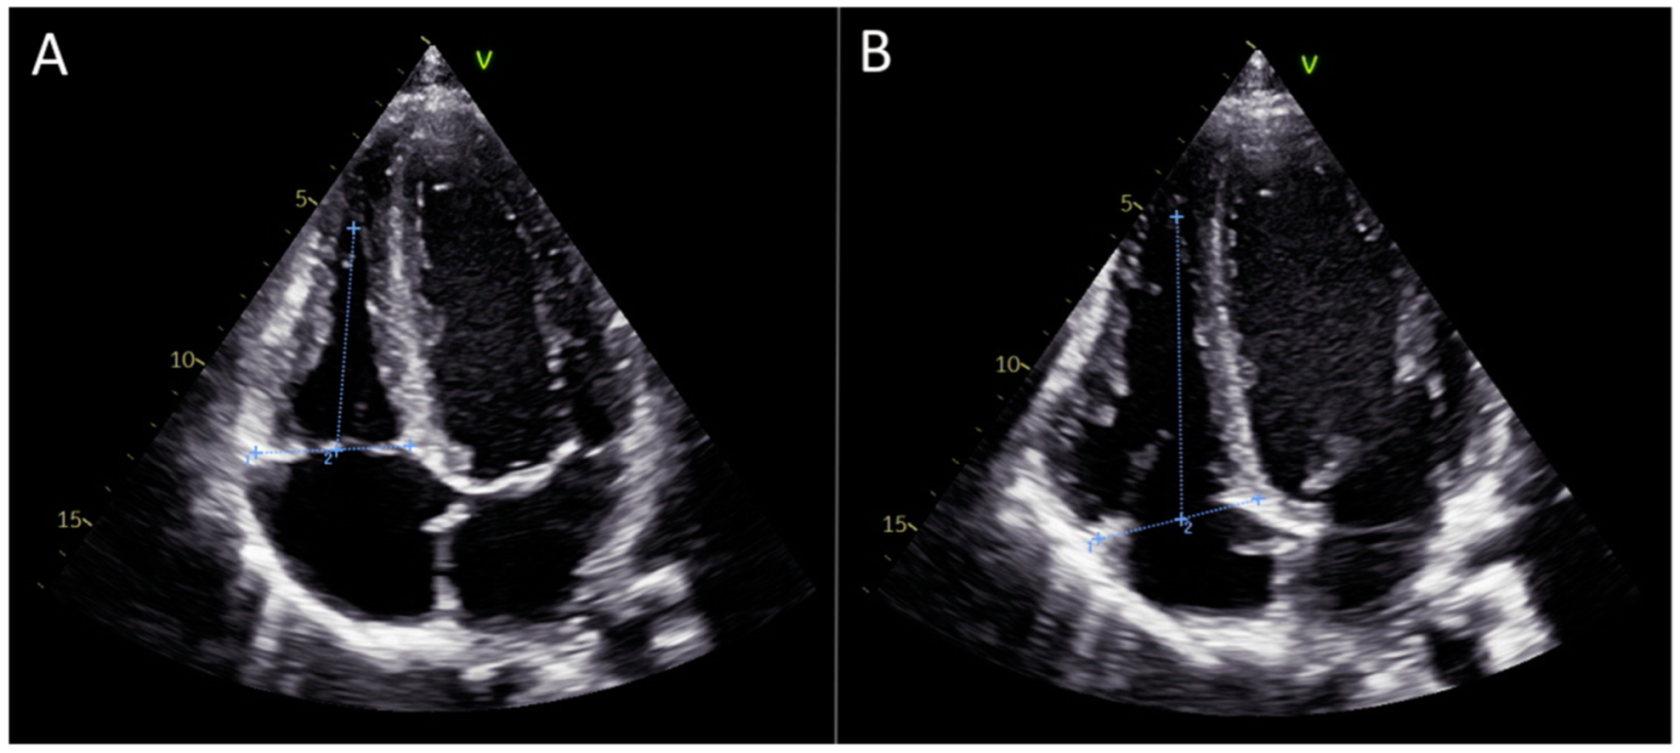

2.2. Specification Regarding Longitudinal Deformation Parameters of the Right Ventricle: Strain and Displacement, Figure 1